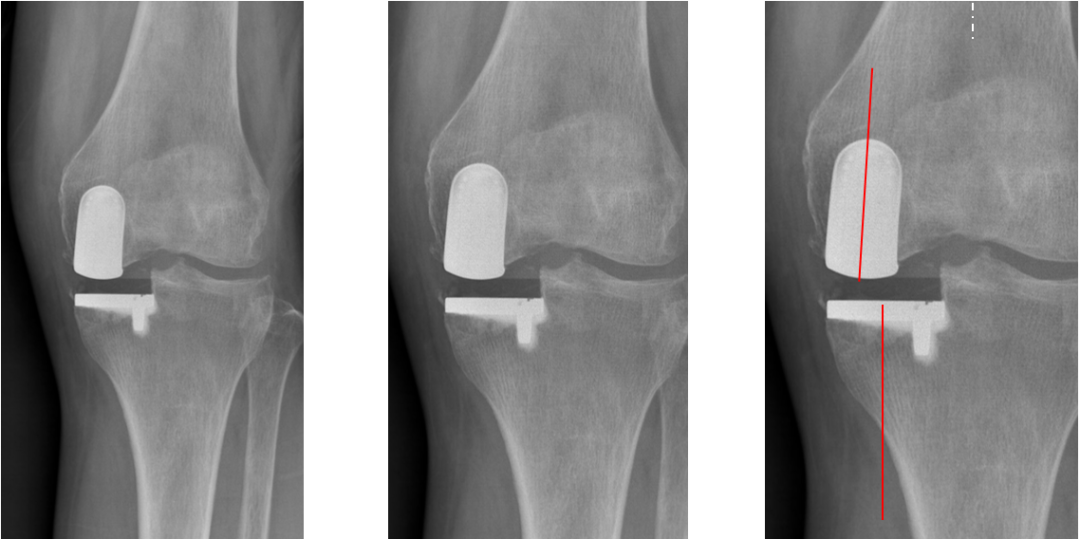

正位片标准胫骨和股骨假体位置

AP位假体位置:胫骨假体无明显内外翻,与胫骨轴线垂直,内侧缘与胫骨平台内侧缘齐平; 股骨假体长轴与胫骨假体垂直,中线一致。

胫骨假体3°内翻

AP位胫骨与股骨假体位置:胫骨假体内翻3°,股骨假体中轴线与胫骨假体垂直。